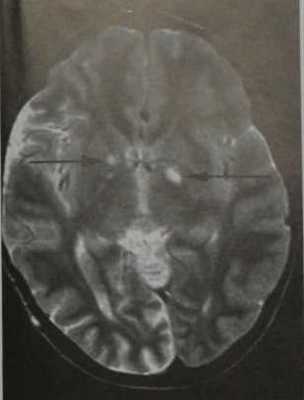

Нейрофиброматоз I типа. МРТ , Т2-Вив аксиальной плоскости. Множественные двусторонние гиперинтенсивные очаги во внутренней капсуле (вакуолизация миелина, стрелкой).

- Гиперинтенсивные очаги на Т2-ВИ в стволе мозга, внутренней капсуле и базальных ядрах, а также в валике мозолистого тела и белом веществе мозжечка

- Отсутствие контрастного усиления после введения КС

- Типично встречается в возрасте старше 3 лет

- Количество и размеры очагов увеличиваются до 10-12-летнего возраста

Вакуолизация миелина: почти никогда не встречается у больных в возрасте старше 20 лет